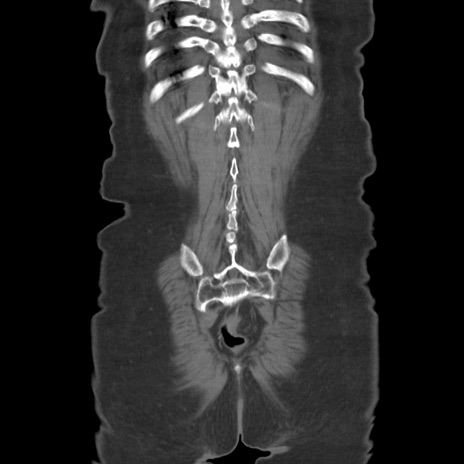

症例19(冠状断像)

【症例】80歳代女性

【主訴】下腹部痛

【現病歴】約8時間前より下腹部痛の出現あり、救急外来受診。

【既往歴】両側付属器切除

【身体所見】意識清明、下腹部正中に手術痕あり、その部位に一致して圧痛と反跳痛あり。腸蠕動音は亢進。

【データ】WBC 9300、CRP 0.15